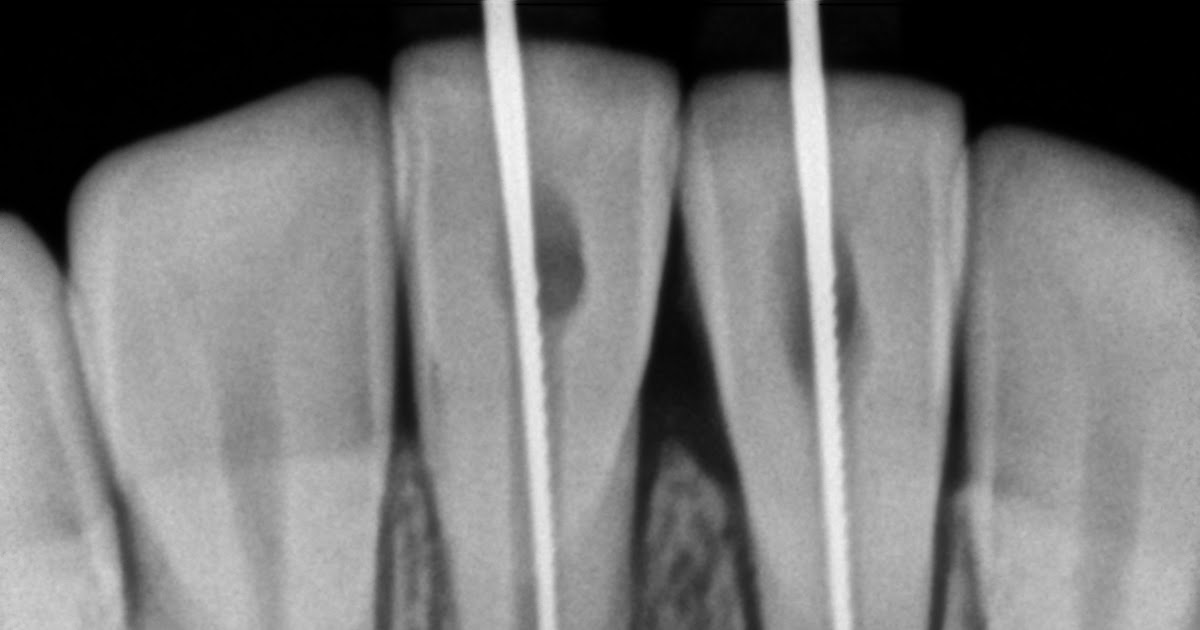

From www.researchgate.net

Master cone radiograph of mandibular left second molar Download What Is Master Cone In Rct Learn how to perform a successful root canal treatment on a lower molar tooth in one visit using nickel titanium files, apex locator, gutta percha and thermoplastic. Design over their active portion. Learn about the materials, techniques and principles of root canal obturation, the final step of root canal treatment. Learn how to fill a root canal with gutta percha. What Is Master Cone In Rct.